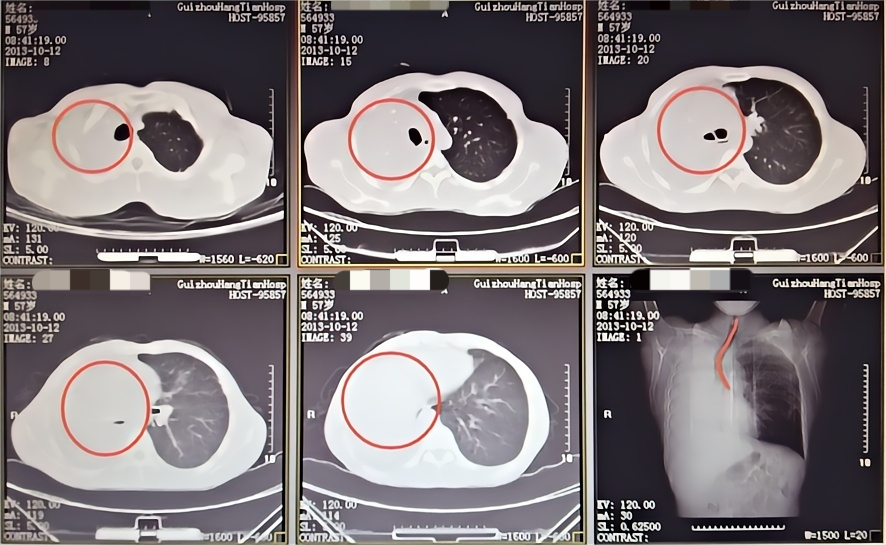

患者潘某某,因咯血在某县医院治疗效果不佳转入我院呼吸与危重症医学科,转入后出现大咯血2次,咯血量近2000ml,患者一度面临生命危险,在科室的充分讨论评估后,决定为患者进行支气管动脉栓塞术止血。

术 前

术 后

在实施支气管动脉栓塞术止血后,考虑到患者大量咯血后血液会阻塞气道,科室团队当即进行CT扫描,发现右肺已被凝血块完全阻塞,立即在床边通过气管镜清理气道内凝血块。术后,患者再无咯血,经住院治疗一段时间后,患者复查CT右肺基本恢复,顺利出院。

大量咳血后CT显示右肺完全阻塞

床边支气管镜清理凝血块

气管镜后复查CT右肺基本恢复